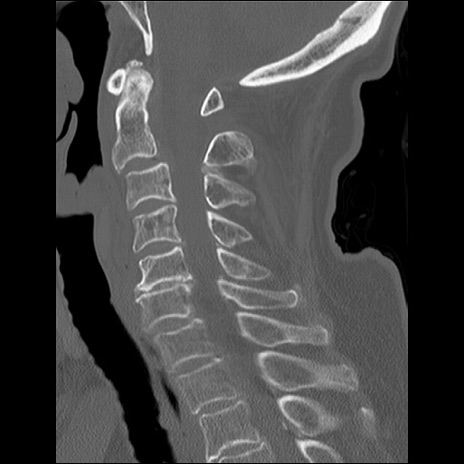

症例48 頚椎CT(矢状断像)

頚椎CT